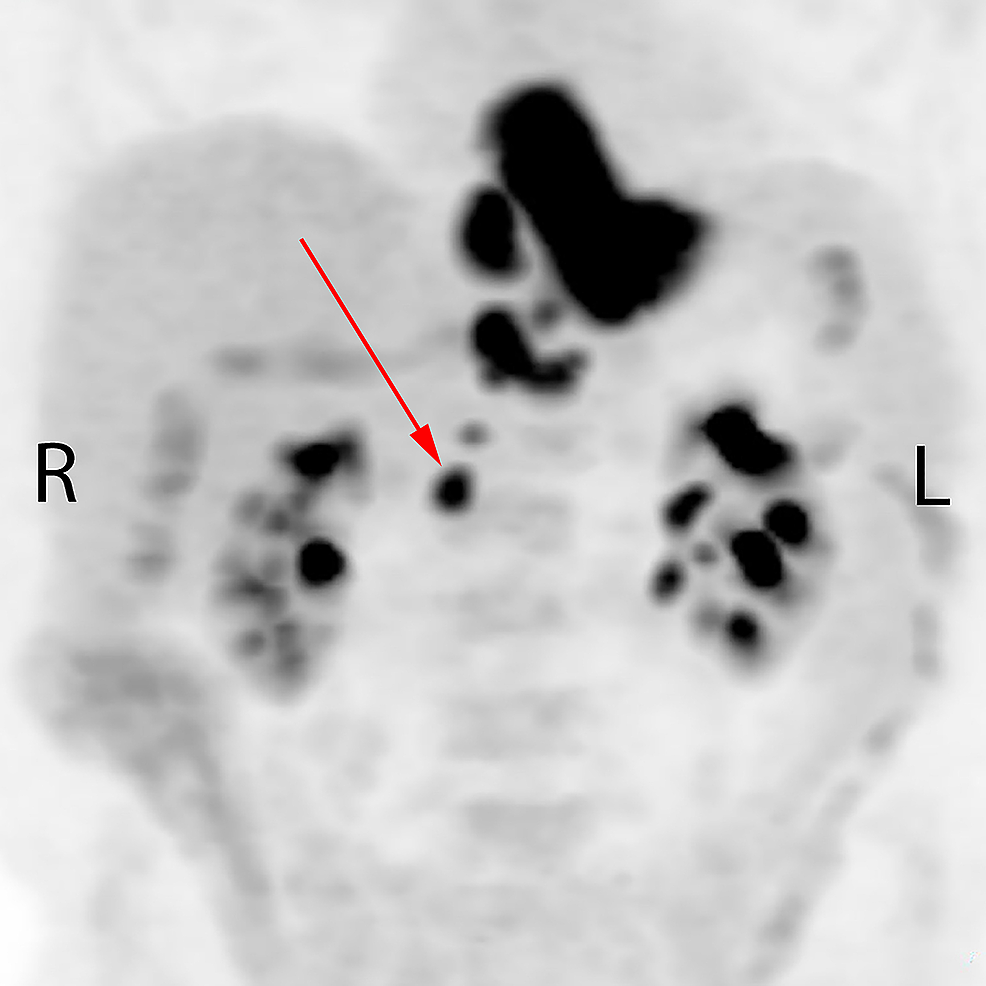

A 74-year-old male presented in February 2016 with increasing dysphagia. There was no history of prior abdominal infection or surgery. On esophagogastroscopy, a necrotic and circumferential friable tumor was seen at 33 to 40 cm from the incisors, with an endoscopic appearance of involvement of gastroesophageal (GE) junction and the proximal 2 cm of the stomach. Biopsies of the distal esophageal tumor confirmed poorly differentiated adenocarcinoma. The patient was anemic with a hemoglobin of 89 g/L. Staging endoscopic ultrasound suggested a breach of muscularis propria and four enlarged paraesophageal nodes. Neoadjuvant chemoradiotherapy followed by esophagectomy was initially considered; however, a staging positron emission tomography (PET) scan demonstrated 18-fluorodeoxyglocose (FDG) uptake not only in the primary tumor, but also in the paraesophageal region near the GE junction and upper abdominal lymph nodes extending as far inferiorly as the right renal vessels, in a retrocaval location (Figure 1).

The patient’s symptom of dysphagia resolved spontaneously, and an evaluation was made with a further PET scan on May 19, 2017 (Figure 3). This demonstrated mild residual FDG activity within the distal esophagus, more likely inflammatory change rather than malignancy. The FDG activity within all the lymph nodes, both treated and untreated, had unexpectedly resolved.